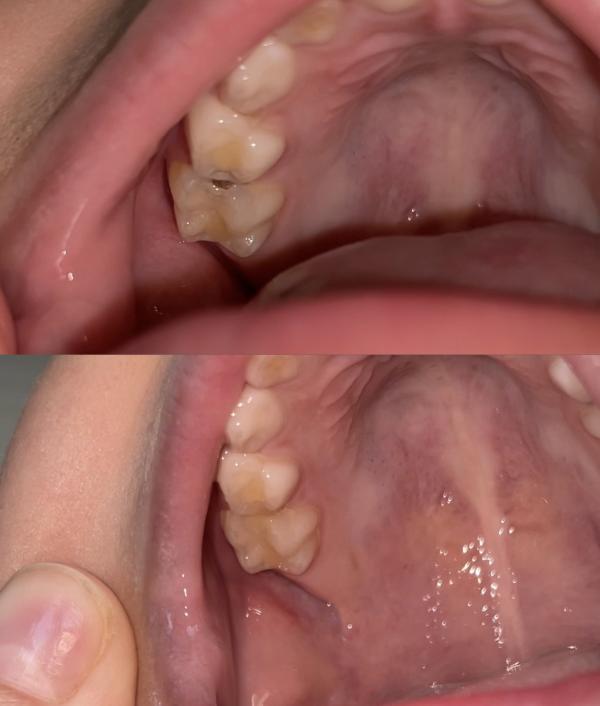

С утра заметила такую черную дырень у сына) сразу записались в Aldent к Жанар Советовне.

До это лечили у нее полгода назад два нижних жевательных зуба.

Тогда я держала его на кресле, сегодня сынок зашел сам уселся, пока я на ресепшене была😅 лечили без моего присутствия, без анестезии. Сразу два зубика сделали, кариес был контактный, быстро распространился.

Отдали 16 тыс, за два зубика